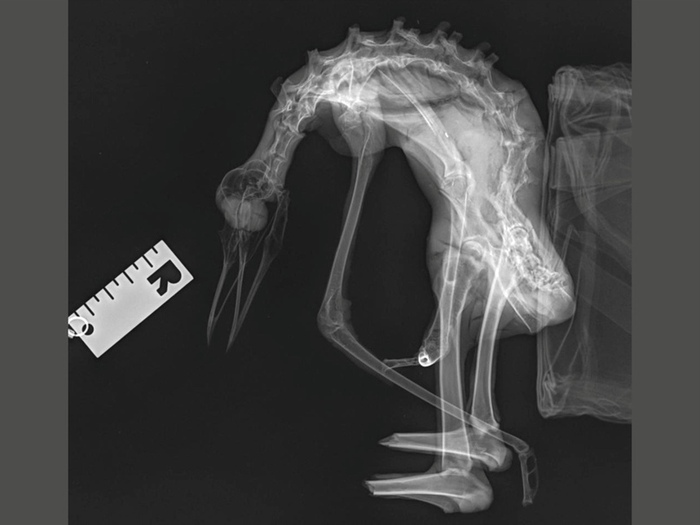

Был сделан рентген. В двух проекциях.

Рентген показал как особенности строения дриопингвина, так и вероятную причину его смерти — сломанный позвоночник. Вероятно, существо прятало тело жирное в утёсах, сорвалось вниз, разбилось и было естественным образом мумифицировано, а потом на этом месте был построен метрополитен.